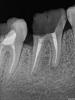

пожалуйста, посмотрите на прилагаемые снимки и посоветуйте, возможно ли в данном случае протезирование ? зубы, правые нижние 6ка и 7ка сильно разрушены... 6ка треснула пополам, а 7ку сильно повредили во время удаления 8ки.

пациенткаpost-13789-1288290419_thumb.jpg